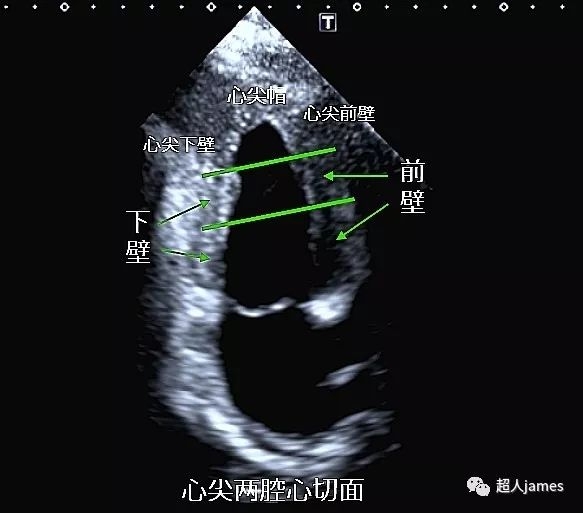

左心室分段图文全解

左心室对于会做心脏彩超的同行来说太熟悉不过了,但是对于大多数人来说真的了解了吗?今天我们主要来聊聊左心室的常用分段方法:

目前,左心室的分段主要有16节段、17节段和18节段几种分法,今天我们先看看16节段到底是怎么分的。